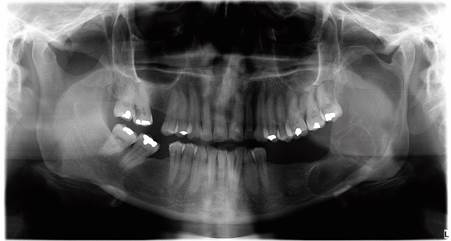

Seis meses después - al observar radiográficamente una disminución del área radiolúcida y aposición ósea (figura 5) - se realizó un nuevo abordaje, esta vez bajo anestesia general, para permitir un curetaje más agresivo y mayor remoción de tejido tumoral. Se realizó una nueva biopsia incisional y se aplicó solución de Carnoy. El resultado histopatológico fue ameloblastoma uniquístico patrón mural con proceso inflamatorio crónico y agudo.